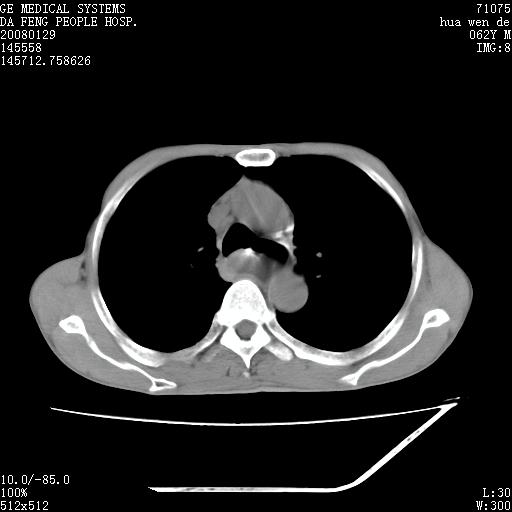

男性,67岁。作肺部检查时发现

理由:1、右上肺内病灶,空洞形成,有液平。

2、肺内多处炎症。

3、前段肺内炎症,支气管引流通畅,与肿块无关系。

1.整个食管扩张,未见明显占位性病变,贲门区亦未见明显占位病变,考虑:贲门失驰缓症;

2.右上肺病变边缘可见毛刺,囊壁厚度不均匀,周围境界较清楚,未见炎性渗出性影,右上肺外带可见片状影,边缘不清,考虑:肺癌伴空洞形成、右上肺炎。

食管全程扩张,壁均匀不厚,喷门失弛缓症

右上肺空洞可见液平,临近肺野磨玻璃密度,考虑1.结核2.脓肿